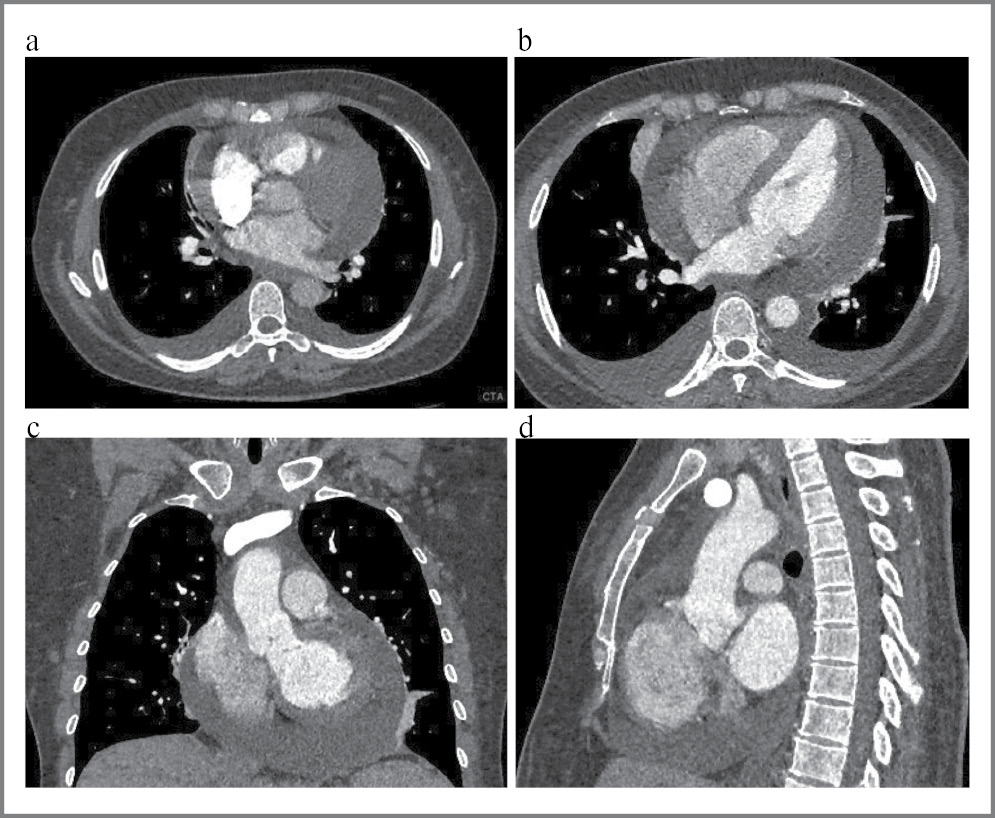

Электрокардиография. Ритм синусовый, частота сердечных сокращений 75 уд/мин, PQ – 0,15 с, QRS – 0,08 с, QT – 0,36 с. Вертикальная электрическая ось сердца (рис. 1).

Рис. 1. Электрокардиограмма больной К.

Fig. 1. Electrocardiogram of patient K.